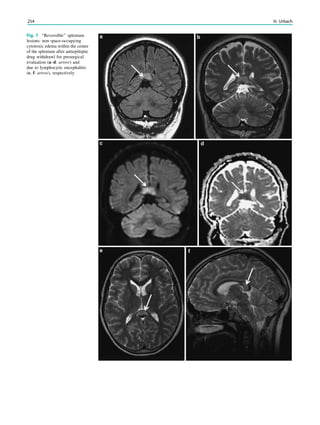

Zentralbl Neurochir 67(4):165–182

Clusmann H, Schramm J, Kral T et al (2002) Prognostic factors and

outcome after different types of resection for temporal lobe

epilepsy. J Neurosurg 97(5):1131–1141

Cross JH, Neville BG (2009) The surgical treatment of Landau–